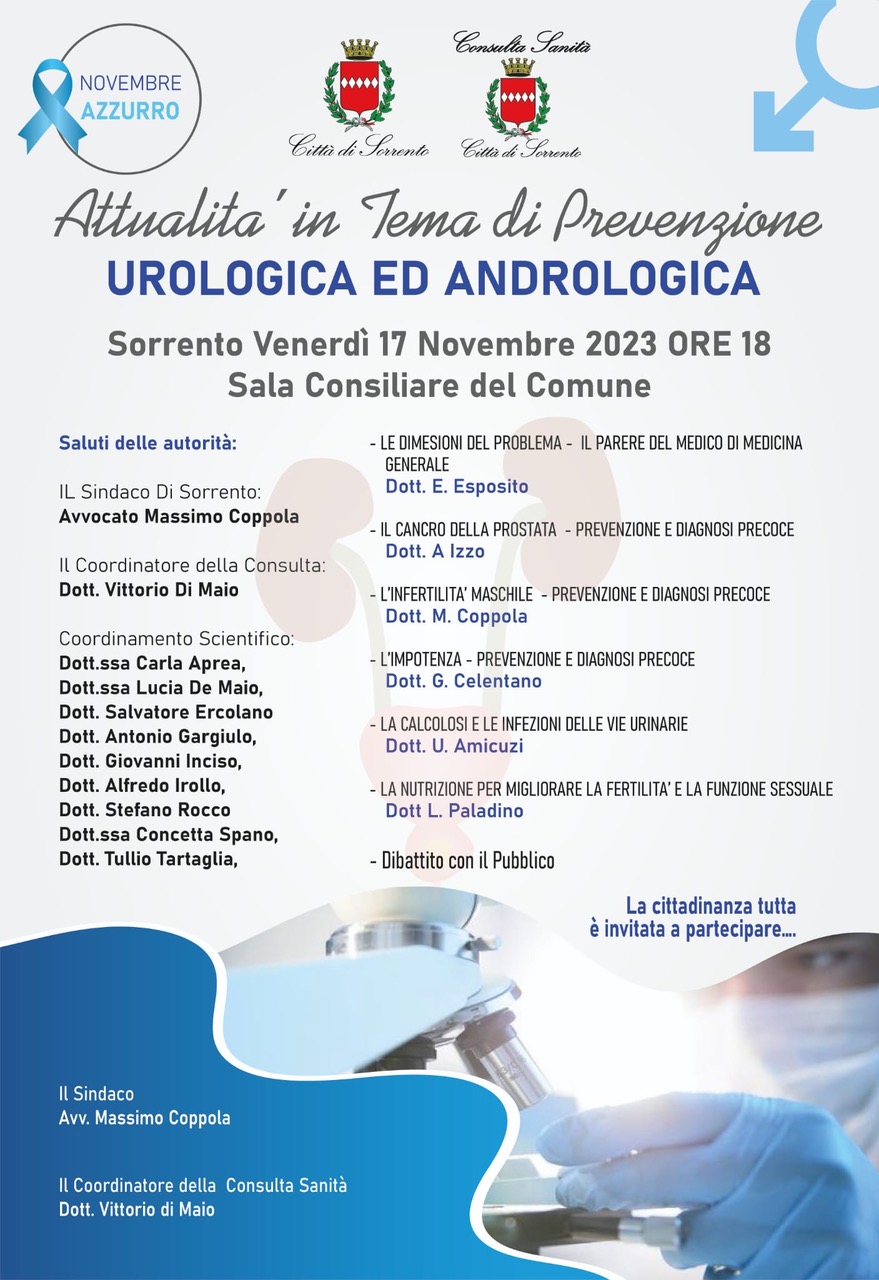

Sorrento

Presso la sala consiliare del Comune di Sorrento, si terrà un incontro sul tema "Perché tanti cesarei?".

Dopo i saluti del sindaco Massimo Coppola, l'intervento del professore Mariano Iaccarino, specialista in Ginecologia ed Ostetricia, Liberato Cafiero, dirigente psicologo presso l'Unità Operativa[...] Vai all'evento